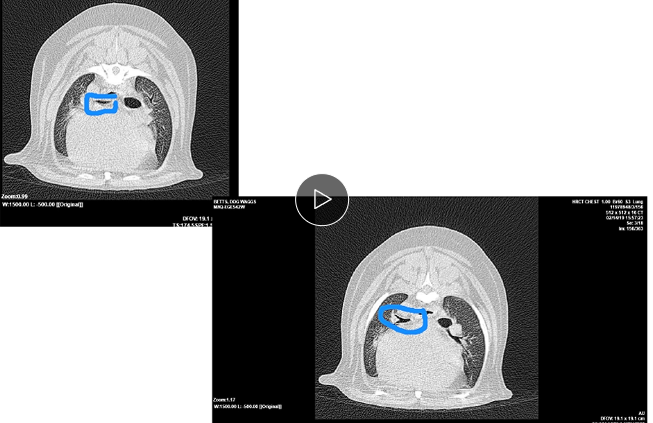

Little area of consolidation but nothing else significant

DX - chronic cough suspicions for airaway disease due to chronic unproductive cough

On left hand side (actually right ariway) airway is compressed

Wouldn’t be ablse to see mass on radiograph as heart borders block ti

Bronchoscopy - wouldn’t be able to see the mass - only see the collapse but not what caused it

CT is our bitch